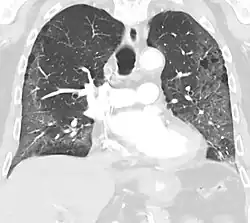

CT image showing patchy areas of ground-glass opacities representing pulmonary edema.

The diffuse pattern typically refers to GGOs in multiple lobes of one or both lungs. Broadly, a diffuse pattern of GGO can be caused by displacement of air with fluid, inflammatory debris, or fibrosis. Cardiogenic pulmonary edema and ARDS are common causes of a fluid-filled lung. Diffuse alveolar hemorrhage is a rarer cause of diffuse GGO seen in some types of vasculitis, autoimmune conditions, and bleeding disorders.[6]